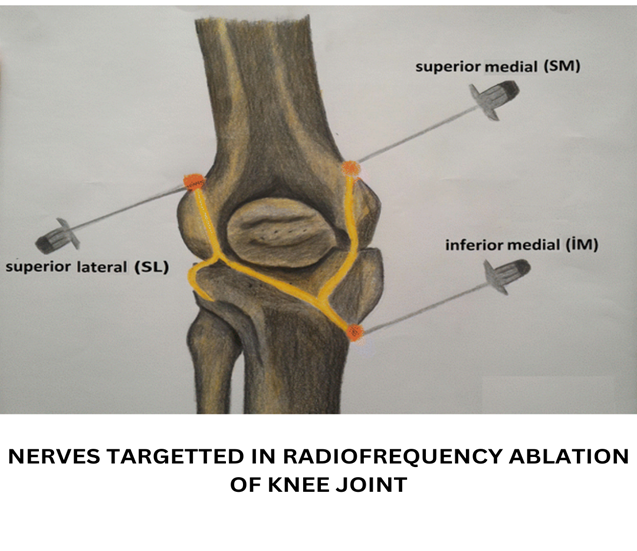

Example 2: Knee pain in osteoarthritis of knee is in part because of synovial inflammation and cartilage degeneration. Nerve supplying the joint are the genicular nerves. We can target the pain generator (synovium and cartilage) by steroid injection that reduces the inflammation and brings relief for 3-6 months depending on the stage of osteoarthritis. PRP injection which is a regenerative therapy can also be given that helps form new healthy cartilage and synovium and brings relief for 9-12 months. Nerve can also be targeted by radiofrequency ablation of the genicular nerves that brings relied for 2.5-3 years. Choice of pain procedure depends on the severity of pain, stage of osteoarthritis and expectations of the patient.

- Radiofrequency ablation of genicular nerves:

- Patient selection: Patients with pain of advanced knee osteoarthritis who are not willing for knee replacement surgery benefit tremendously with this technique.

- Technique: Genicular nerves namely superior medial nerve, superior lateral nerve and inferior medial nerve carries the pain of knee. They are ablated by radio frequency energies using an instrument called radio frequency ablation. The procedure is performed in local anaesthesia.

- Expected results: The pain relief last for 2.5-3 years after which the procedure can be repeated.